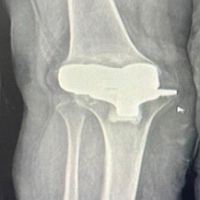

Stage 2 included removal of the antibiotic spacer and implantation of a new prosthesis (Fig. 3). Due to the absence of identifiable abductor musculature intraoperatively, a constrained acetabular cup was utilized. The 1st post-operative week was uneventful. However, by the end of the 2nd post-operative week, the surgical site dehisced with purulent discharge. Subsequently, the entire greater trochanter became exposed and devitalized, with concurrent exposure of the trunnion (Fig. 4). In consultation with a plastic surgeon, the decision was made to proceed with DAIR and flap coverage. All devitalized bone was debrided until healthy bleeding points were observed (Fig. 5). Simultaneously, a musculocutaneous anterolateral thigh flap was raised and inset by the plastic surgery team (Fig. 6). Multiple drains were placed. Postoperatively, the patient received intravenous piperacillin-tazobactam and linezolid for 6 weeks. Culture of intraoperative samples was negative. Sutures were removed on post-operative day 14. The patient was advised to remain on non-weight-bearing mobilization from post-operative day 2. Hip range-of-motion exercises and partial weight-bearing ambulation were initiated during the 3rd post-operative week, progressing to full weight-bearing by the 6th week. At the 3-month follow-up, the flap had healed successfully (Fig. 7). Inflammatory markers at that time were CRP 4.1 mg/L and ESR 28 mm/h. Post-operative radiographs were obtained at 6 weeks, 6 months, and 12 months (Fig. 8). At the most recent follow-up (12 months), the patient was ambulant with walker support and doing well clinically.